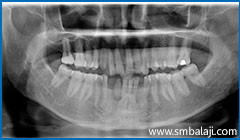

X-ray showing teeth impacted in the lower right jaw region

Impacted teeth surgically removed